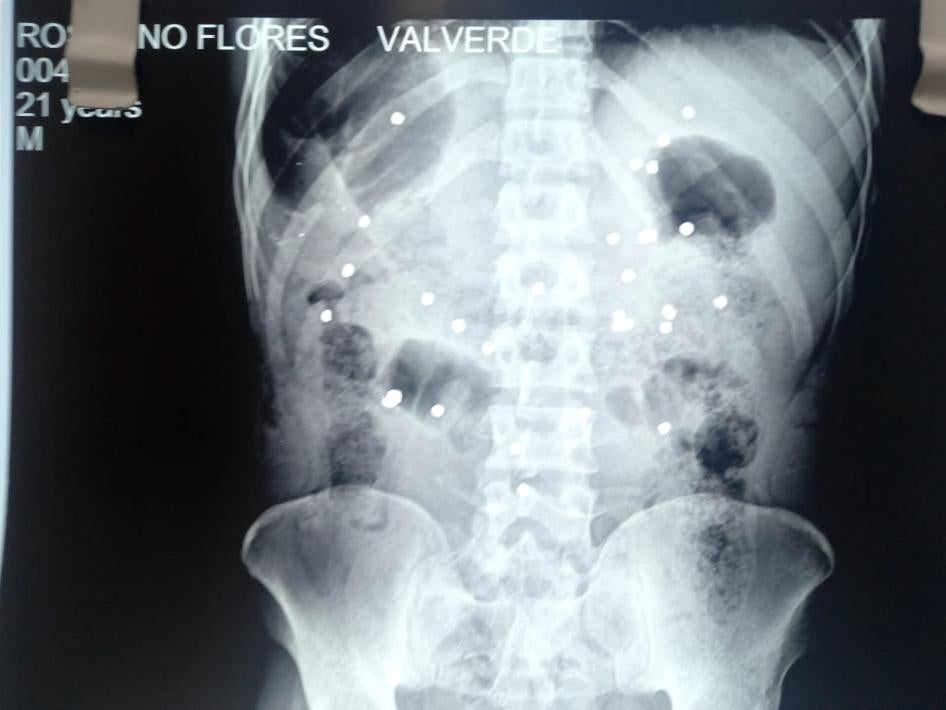

Pellets that police fired from shotguns caused injuries in January 2023 that killed at least five people in Juliaca, Arequipa, and Cusco. Victims were hit by multiple pellets, indicating they were shot at close range, as this type of projectile scatters with distance. In one case, CCTV footage verified by Human Rights Watch shows a police officer shooting at a young man from roughly seven meters away, as he fled. An X-ray showed about 30 pellets in his body. He died in March 2023. At least 71 people were injured by pellets, Ministry of Health data show.